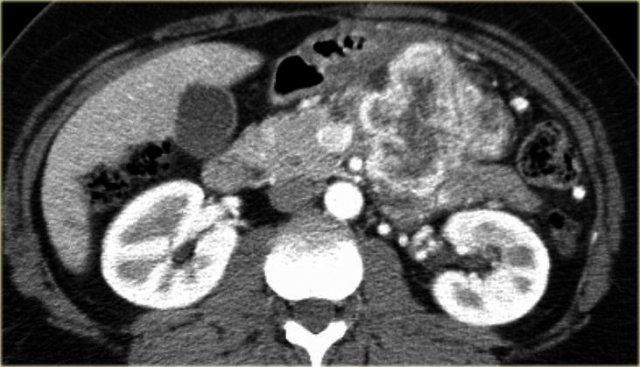

CT-images of a 61 year old woman with weight loss.

There is a large mass in the body of the pancreas that is hypervascular, unlike an adenocarcinoma, with some cystic or necrotic parts.

CT-image of a neuroendocrine tumor with central necrosis.

Sometimes this can simulate a cystic component.

Notice the peripheral enhancement.